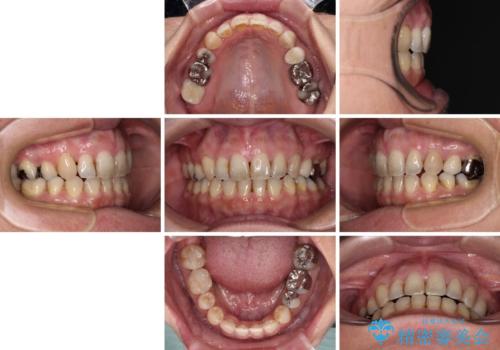

上顎左右第1小臼歯を抜歯したことで、隙間が閉じた下顎歯列の位置まで前歯を引っ込ますことができたため、口の閉じにくさを解消することができました。